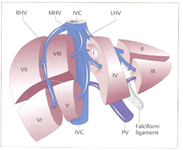

Figuur 4: 1. alvleesklier, 2. maag. 3. 12-vingerige darm, 4. lever links, 5. lever rechts, 6. galblaas, 7. hoofdgalweg, 8. poortader, 9. poortader rechts, 10. poortader links, 11. lever slagader, 12. lever slagader rechts, 13. leverslagader links. Bron: Amsterdam UMC

De lever zelf bestaat uit 2 delen. Een linker helft en een rechter helft (zie figuur 4). Elk deel bestaat weer uit kleinere delen, segmenten genaamd (zie figuur 5). In totaal heeft de lever 8 segmenten. Ieder segment (deel) heeft een eigen bloedvoorziening en gal afvoersysteem (zie figuur 6).

De lever zelf bestaat uit 2 delen. Een linker helft en een rechter helft (zie figuur 4). Elk deel bestaat weer uit kleinere delen, segmenten genaamd (zie figuur 5). In totaal heeft de lever 8 segmenten. Ieder segment (deel) heeft een eigen bloedvoorziening en gal afvoersysteem (zie figuur 6).

Figuur 5: Bron NTVG

Figuur 6: Bron: John Hopkins Medical Centre